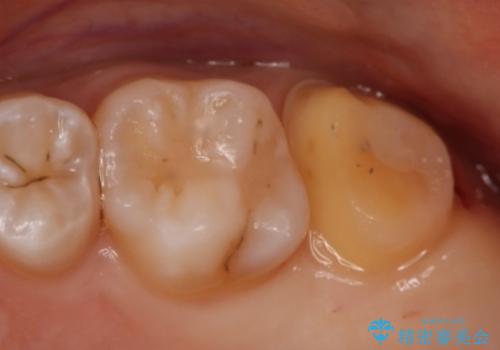

- 左上7番の虫歯治療を主訴に来院された患者様です。

虫歯の範囲が広かったので切削量・形態を考慮し、セラミッククラウンでの治療を計画しました。

虫歯の範囲が広い場合、大きく削る必要があるので部分的に詰めるインレーではなく、クラウンでの治療になることがあります。